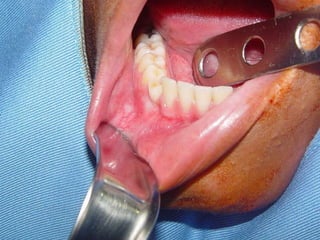

Granuloma (Lesão) Periférico de Células Gigantes A excisão cirúrgica deve ser antecedida de exame radiográfico, pois lesão não completamente removida e/ou com infiltração óssea, pode recorrer

Granuloma (Lesão) Periféricode Células Gigantes A excisão cirúrgica deve ser antecedida de exame radiográfico, pois lesão não completamente removida e/ou com infiltração óssea, pode recorrer